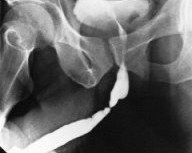

Травма уретры проявляется уретроррагией, острой задержкой мочи, образованием гематом на промежности или в глубине таза. Наиболее полное представление о характере повреждения мочеиспускательного канала дают рентгенологические методы исследования и, в частности, уретрография.